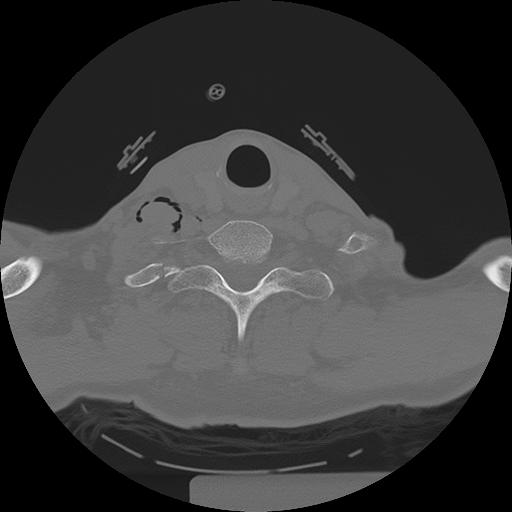

11 HUESO,,Axial,2.0,HUESO,,